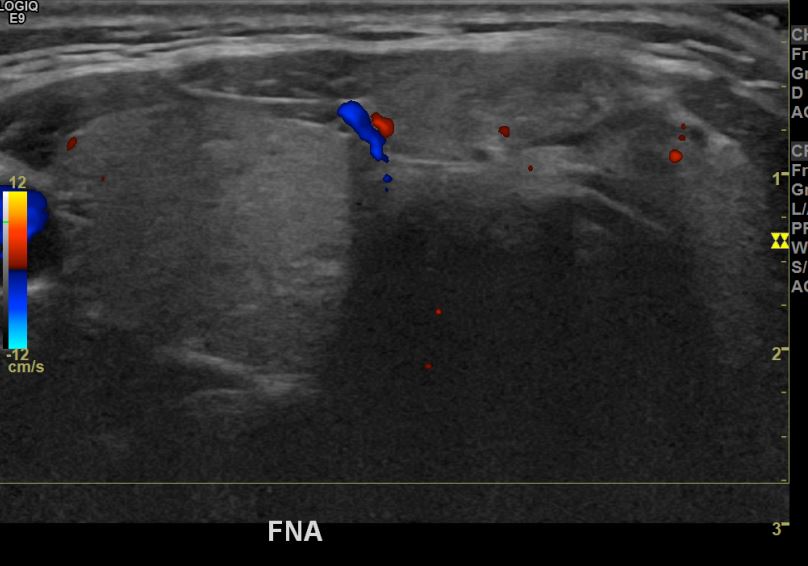

상기환자 외부검진이상으로 내원하신 30대후반 여성분으로 의심스러운혹 세포검사진행후 갑상선암으로 진단되었습니다